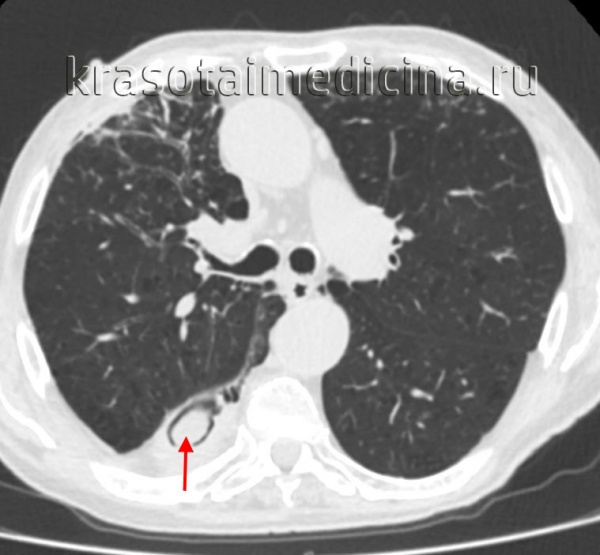

В основном мицетома гайморовой пазухи образуется тогда, когда через сообщающийся канал зуба в неё попадает пломбировочный материал. В состав пломбы входят оксид цинка и сульфат бария, образующие пищевую среду для аспергиллов, что провоцирует развитие мицетомы.

![Пломбировочный материал в гайморовой пазухе [15]](/pimg3/diagnostika-mitsetomi-lechenie-FBBC92.jpeg)

Мультиспиральная компьютерная томография остаётся эффективным и единственным способом диагностики мицетомы околоносовой пазухи. Использование трёхмерной реконструкции даёт представление об объёмном взаиморасположении костей, позволяет оценить состояние верхнечелюстной пазухи и зубочелюстной системы (целостность зубов, степень разрушения, цвет, положение в зубном ряду, подвижность, глубину зубодесневых каналов), а при наличии инородных тел точно показывает их форму, размер и местонахождение.